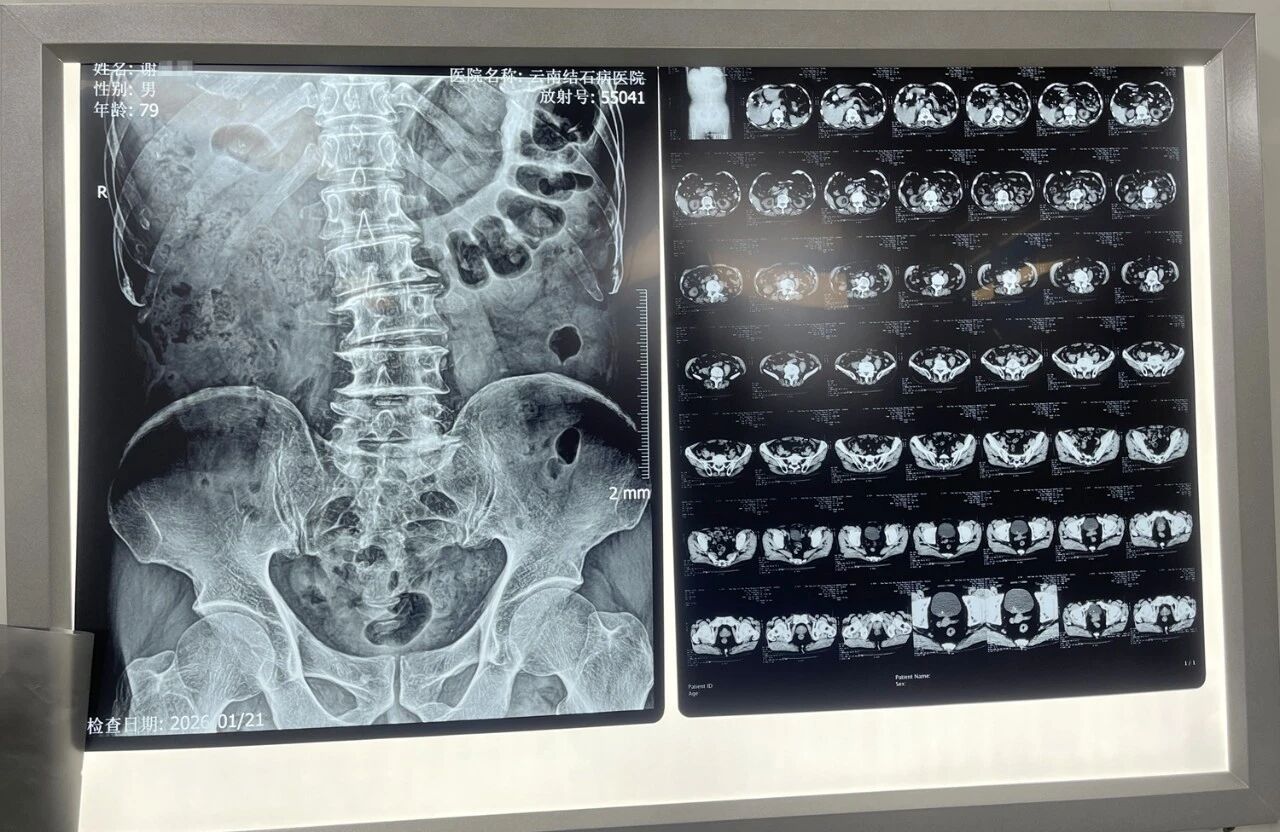

79岁患者谢大爷,近三年来长期受尿频、尿急、排尿不畅等症状困扰,夜间起夜频繁,在当地医院被诊断为“前列腺增生”,多次尝试药物治疗,均未见明显效果。今年元旦过后,谢大爷病情进一步加重,夜尿次数明显增多,并反复出现右腰胀痛症状。再次入院检查,他被诊断为“右输尿管下段结石并右肾积水、前列腺增生”,医生提醒需及时手术。

入院后,黄鸿宾主任团队对谢大爷进行了系统评估。面对患者复杂的病情——既需处理前列腺增生导致的严重排尿障碍,又需解除输尿管结石引发的肾积水,黄主任制定了"融合手术"个性化方案:首先采用瑞梦热蒸汽消融术处理前列腺左右两叶增生组织,随后通过经尿道双极等离子电切术切除中叶突入膀胱部分,最后以微创技术击碎取出右侧输尿管下段结石,彻底解除肾积水。